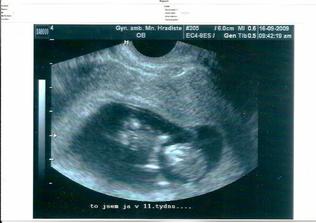

Dnes 25.9.2009 musel být ukončen kraťounký život našeho vytouženého mimíska. Kvůli závažné vývojové vadě neslučitelné se životem. Sbohem, broučku. Moc jsme se na Tebe všichni těšili. Moc jsme to oplakali. Snad se ještě někdy setkáme. Máma, táta, ségra a brácha.